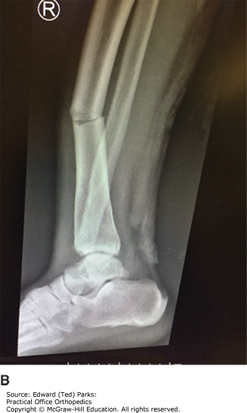

Tibia and Fibula (Tib-Fib) Fracture on X-ray

An AP (A), and lateral (B) x-ray of a tibia and fibula (tib-fib) fracture demonstrating how the fracture can appear well aligned on one view and displaced on the other. When getting x-rays to evaluate an injured extremity, it is important to obtain at least two views at 90 degrees.